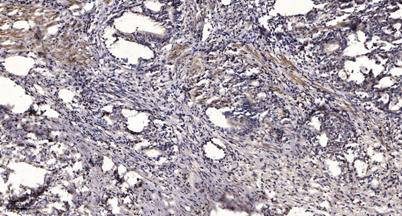

IHC

Recomended Dilution Immunohistochemistry: 1/100 - 1/300. ELISA: 1/5000. Not yet tested in other applications.